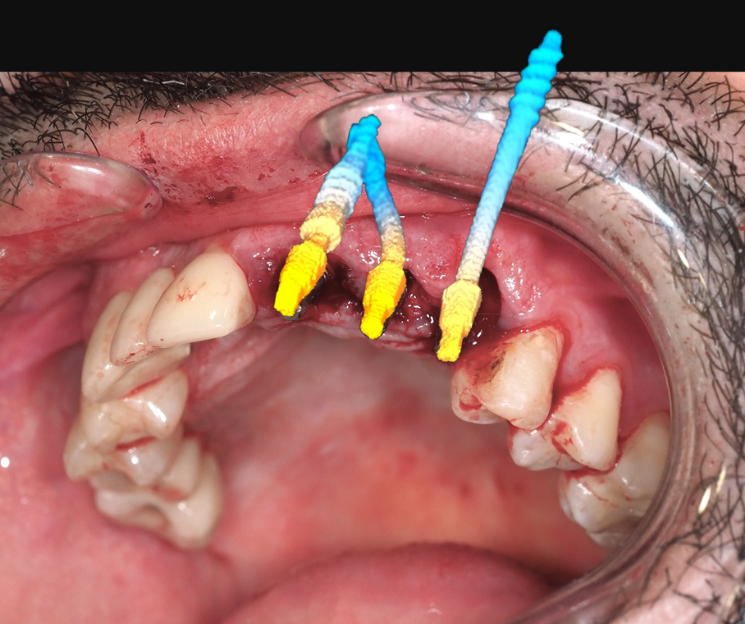

Extracción de piezas 21, 22 y 23 con infección activa

Paciente con infecciones de origen dental que comprometían severamente el hueso alveolar en la zona anterior superior. Se realizó la extracción de los dientes 21, 22 y 23, y se optó por una rehabilitación inmediata mediante implantes córticobasales.

Estrategia protésica e implantes utilizados:

- 1 implante córticobasal compresivo

- 2 implantes córticobasales rectos y finos

Esta combinación permitió anclar los implantes en hueso cortical, que mantiene su estabilidad incluso en presencia de procesos infecciosos en el hueso alveolar. El resultado: rehabilitación funcional y estética el mismo día de la cirugía.